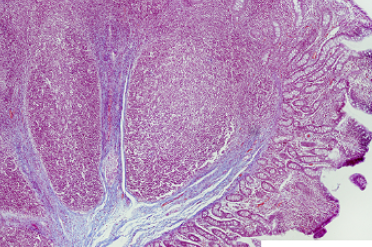

ganglion of submucosal ganglion

the white things

goblet cells